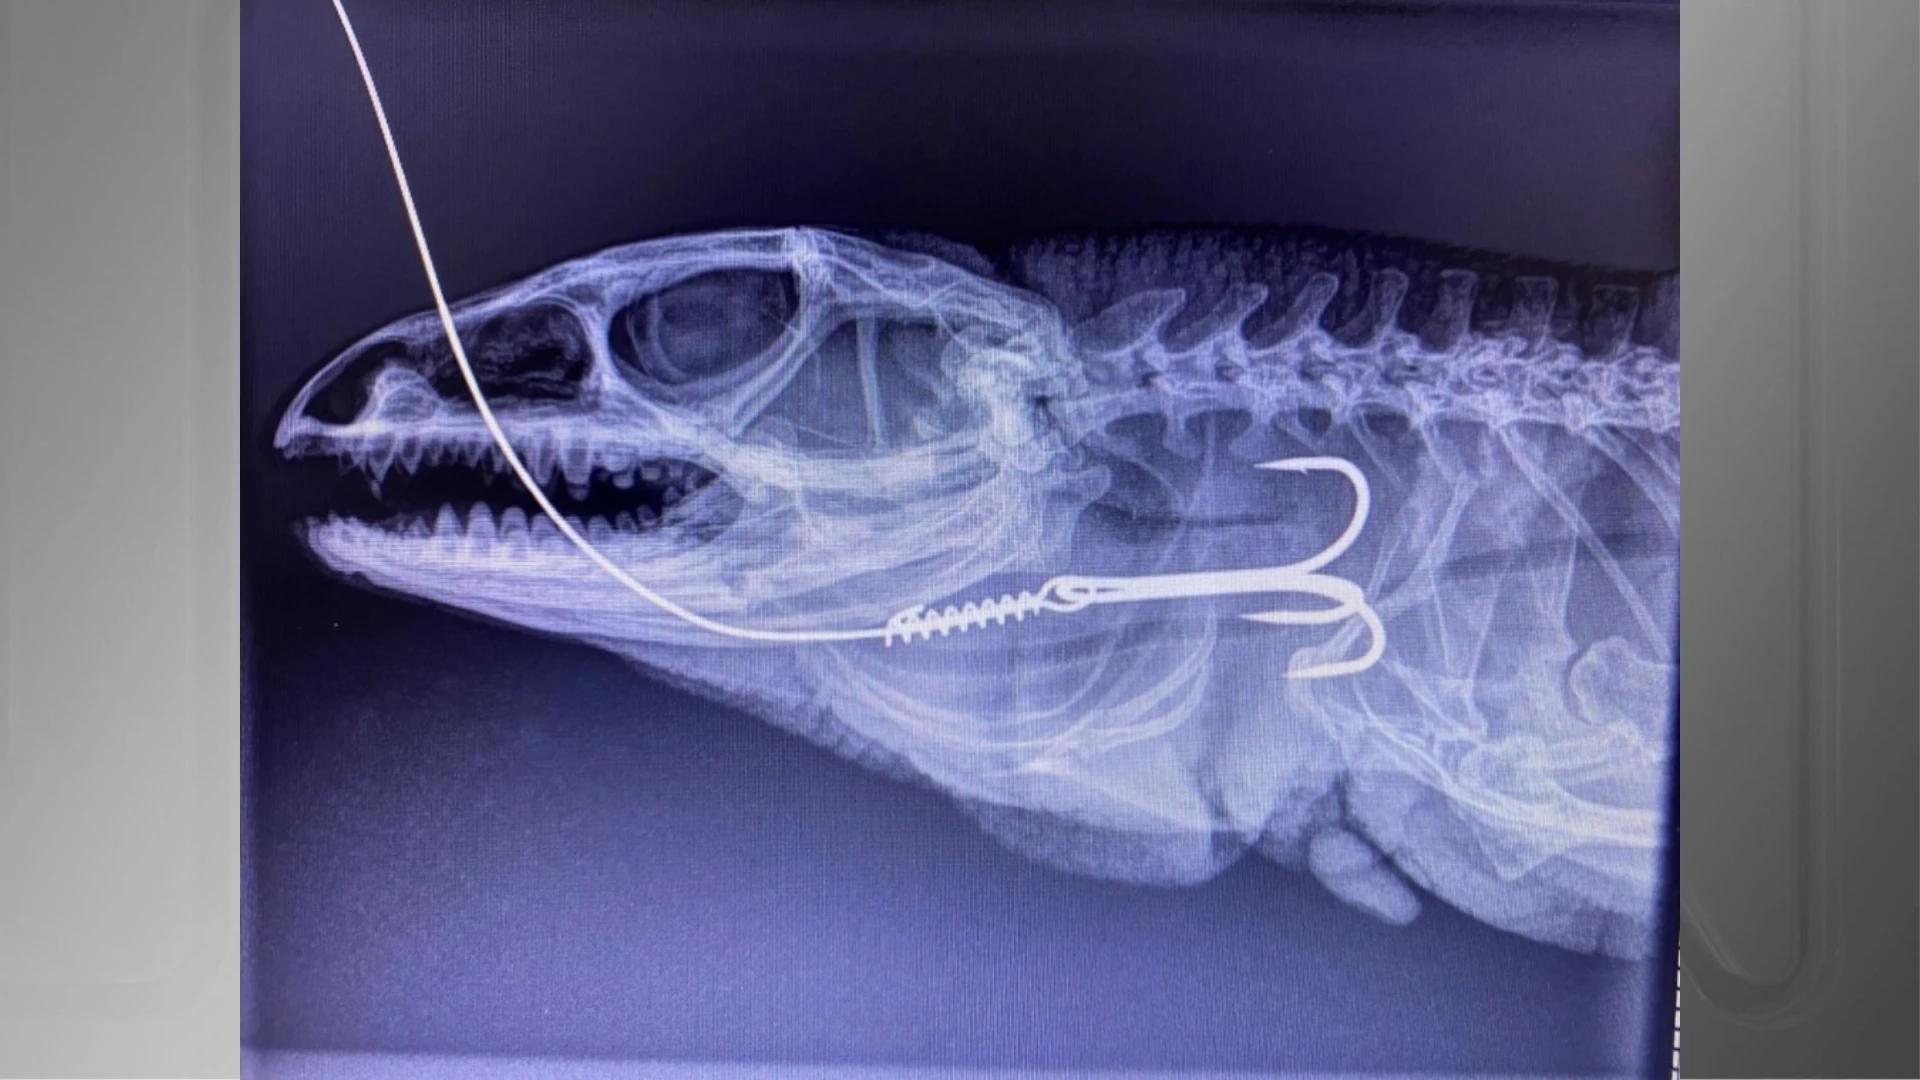

De acordo com Júlio Souza, coordenador do serviço mencionado, o teiú passou por uma cirurgia de esofagostomia, que é um procedimento utilizado para acessar o esôfago e remover objetos estranhos, como foi o caso do anzol. Após essa intervenção, uma segunda cirurgia foi realizada para reconstruir o esôfago do animal, que é uma parte vital do sistema digestivo. Infelizmente, o pós-operatório revelou complicações, e os veterinários perceberam que o lagarto apresentava uma ruptura próxima à entrada da cavidade celomática.